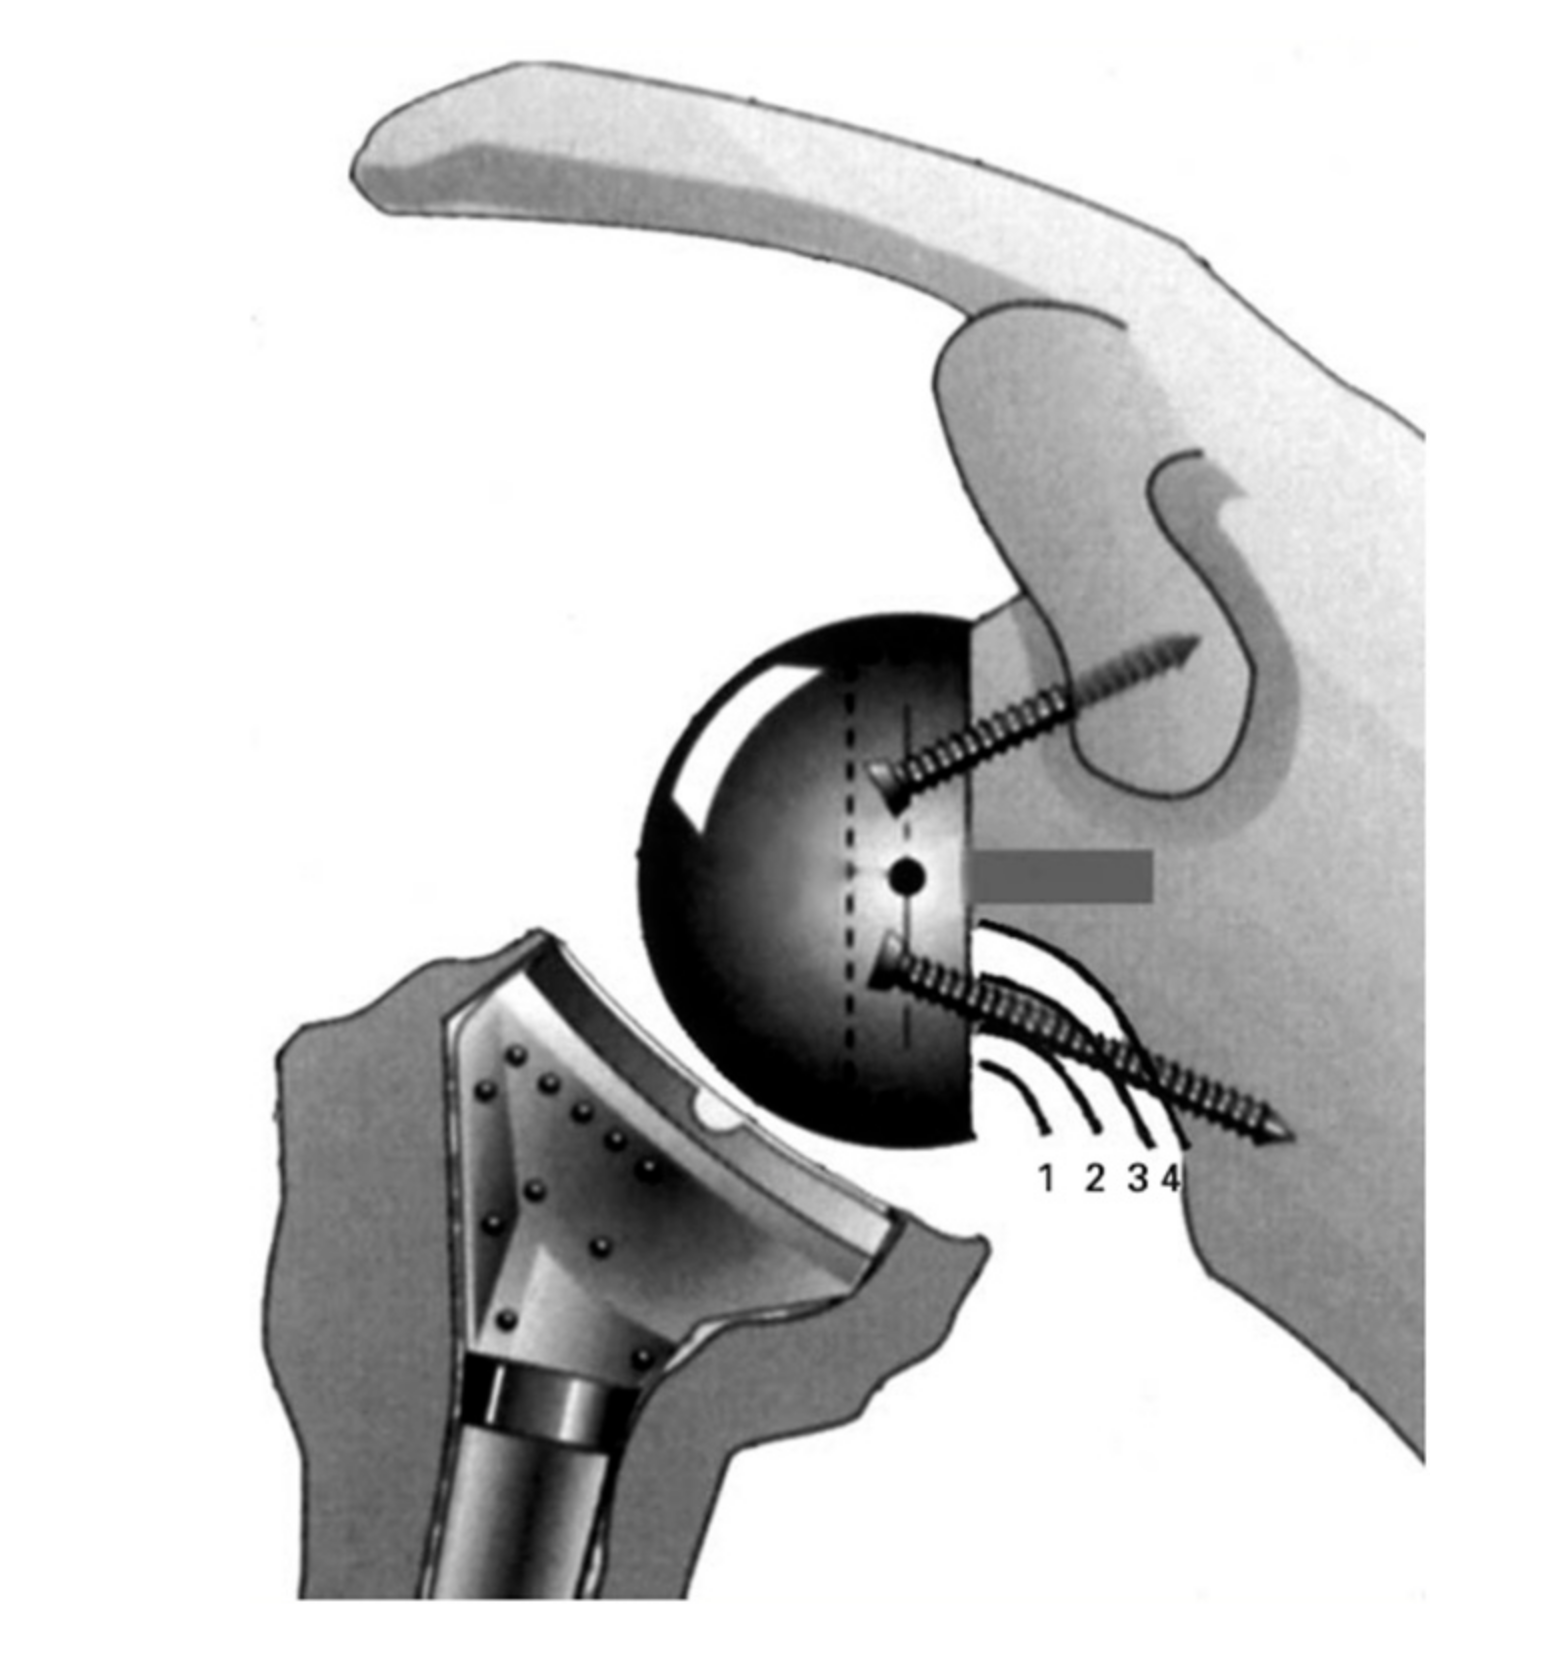

2. Traditional Grammont Design

3. Notching

4. Lateralization (Global)

4.1. Glenoid Lateralization